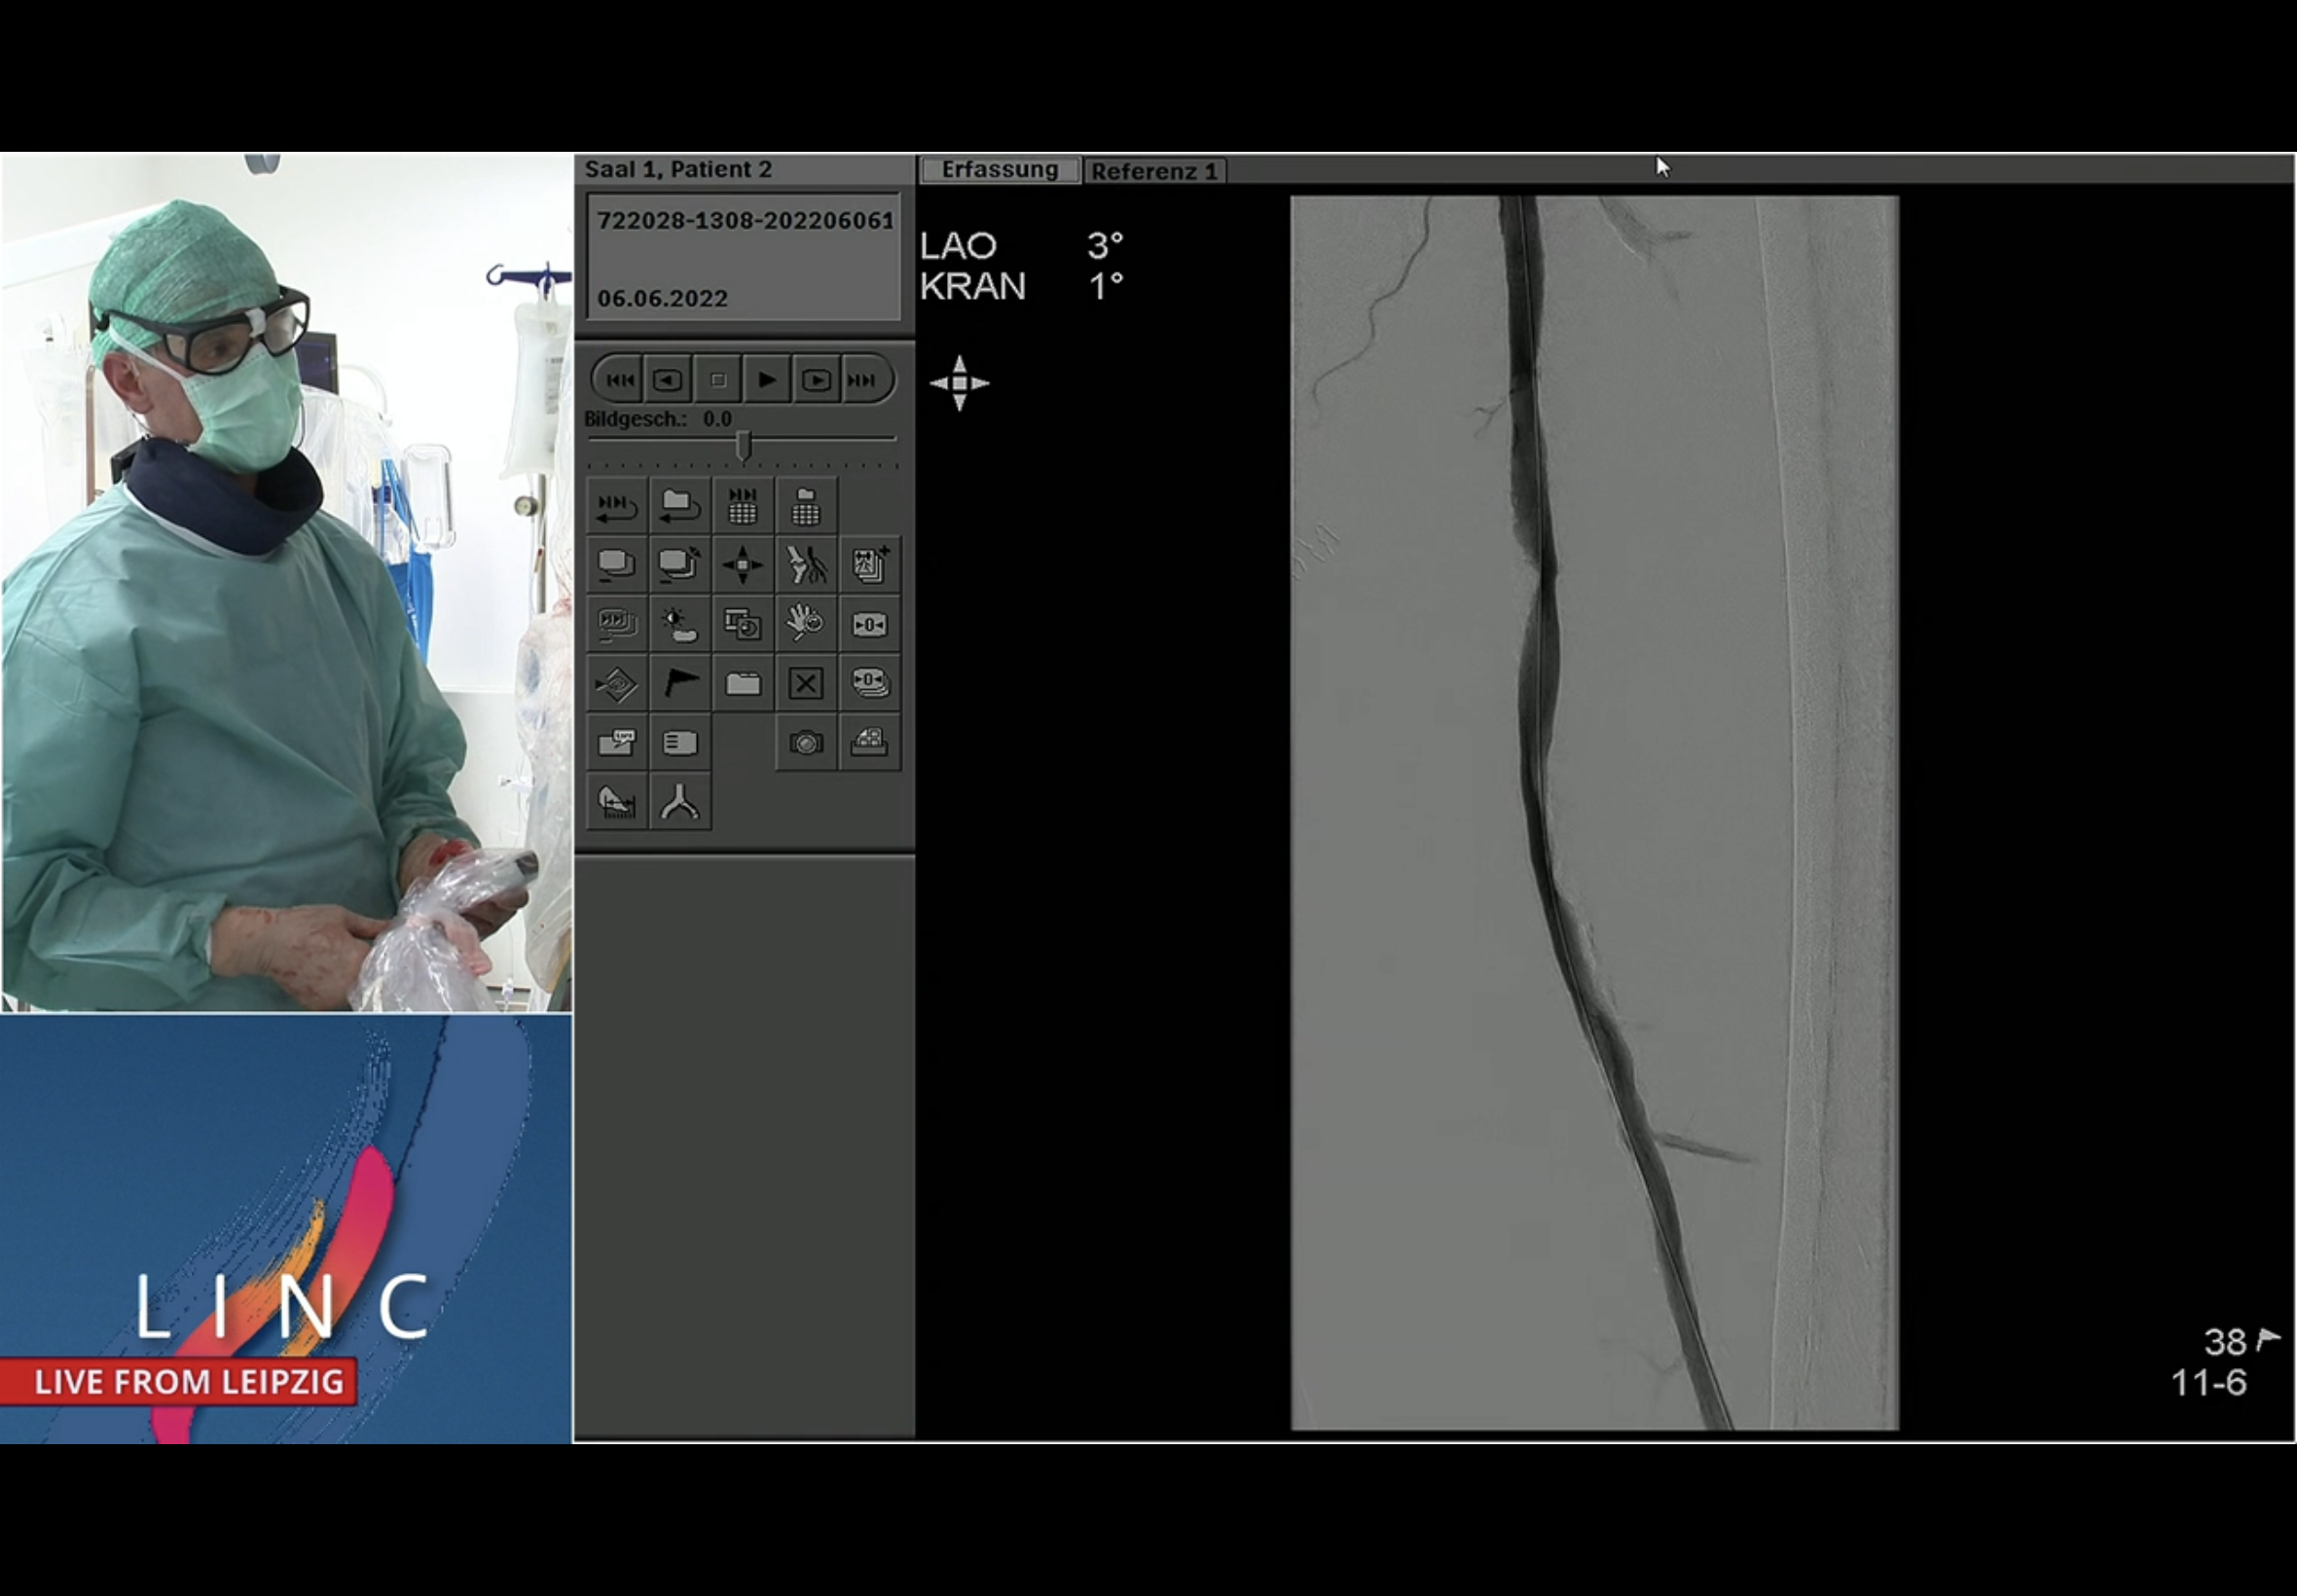

Live Case Leipzig @ 13:50 on Tue. DA + DCB in complex SFA Pop Jun 7 Written By Sean Matheiken Sean Matheiken